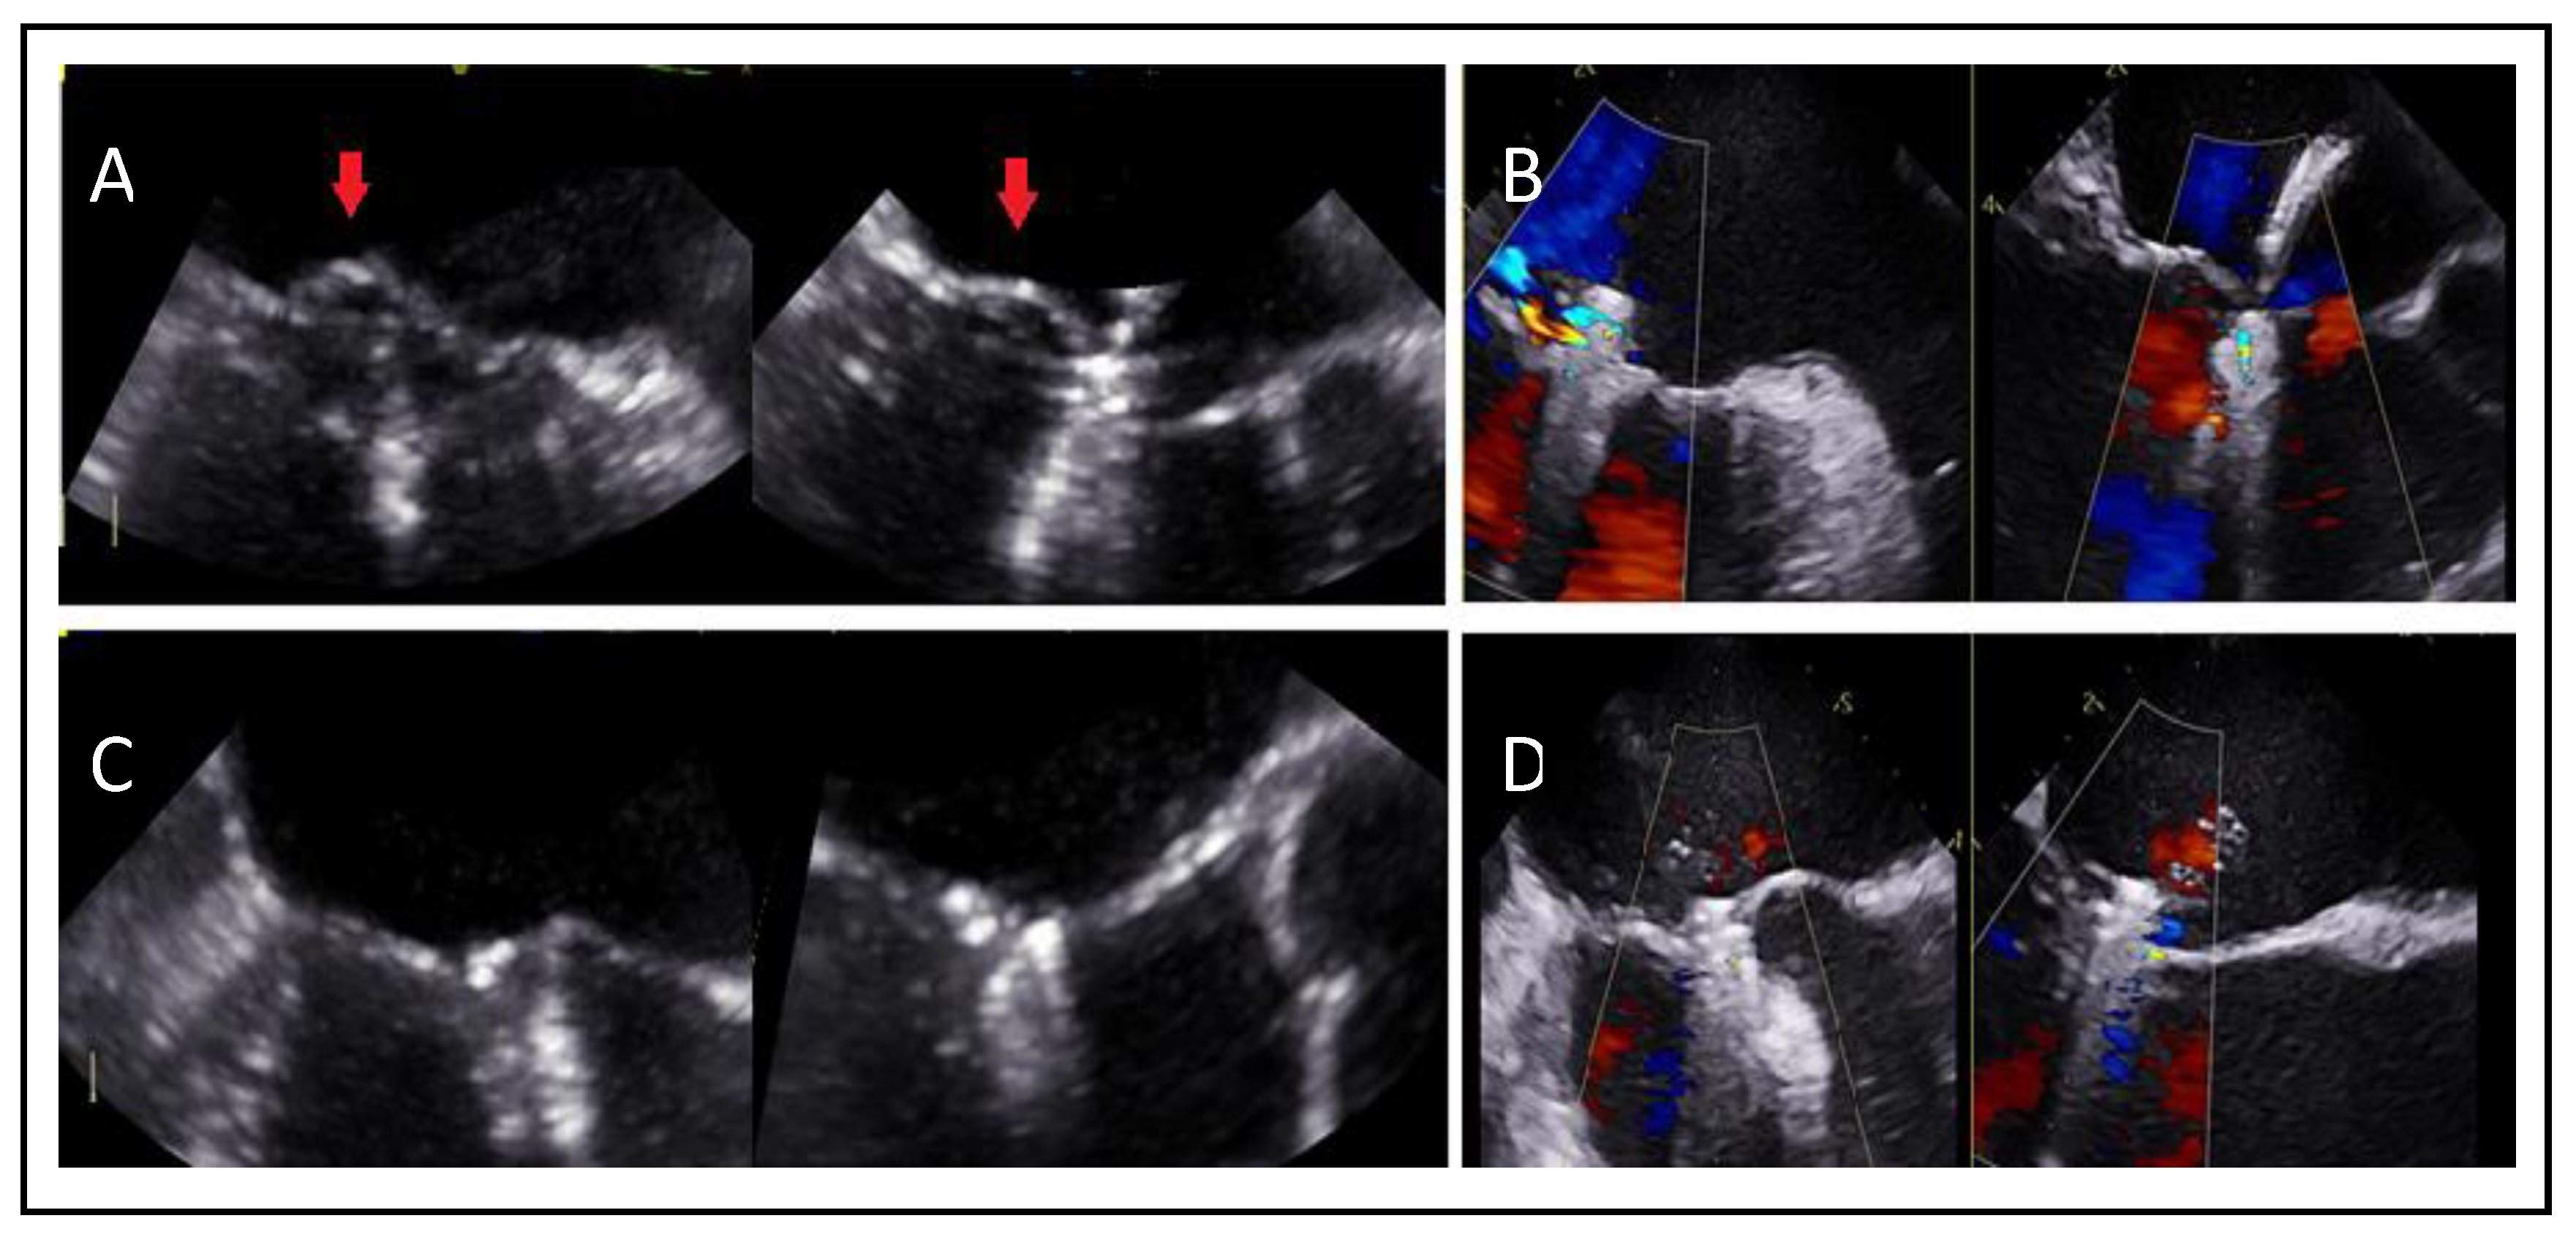

Adequate but Tethered LeafletsPosterior leaflet length may be sufficient, but severe tethering reduces coaptation and grasping success (Figure 11).